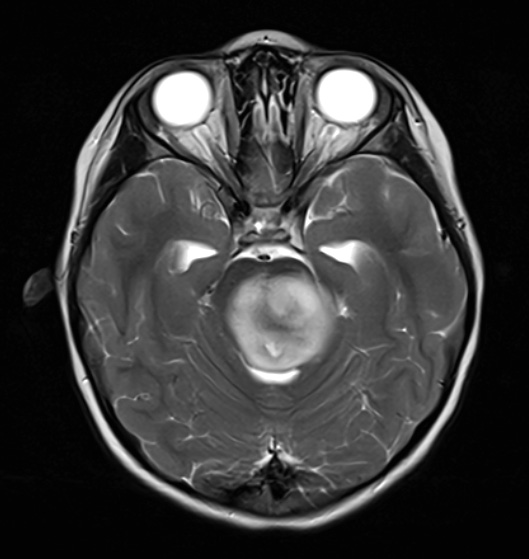

A T2-weighted scan with contrast shows a hyperintense mass.